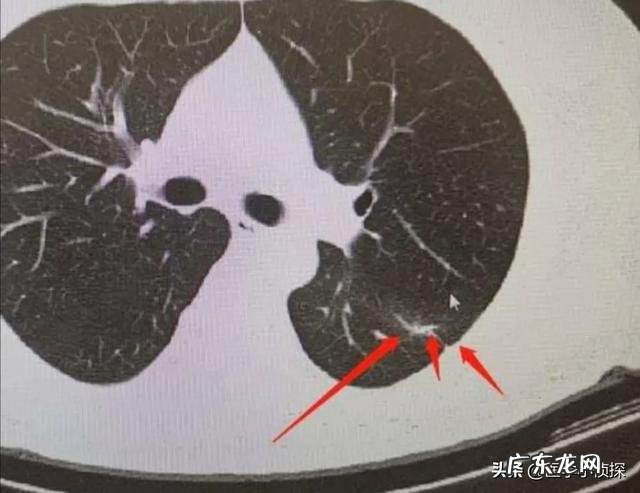

假如你胸部CT检查出肺结节 , 重点关注报告单上这些内容 , 基本上不用过于担心肺结节最后会发展为晚期肺癌!